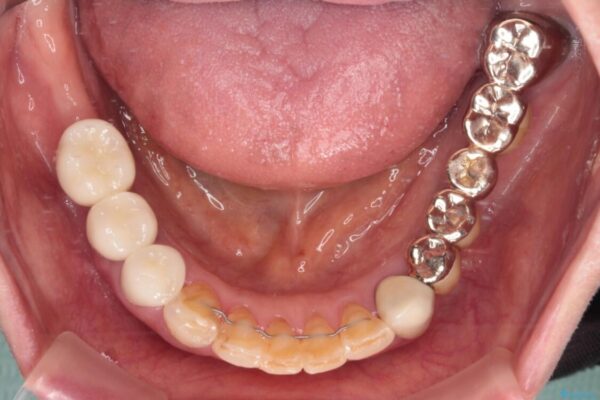

治療後

• 前歯をきれいにしたい インプラントや部分矯正を用いた総合歯科治療 治療後画像

処置を予定していた歯を仮歯に変えた時点で、下顎前歯の部分矯正を行うかどうかを尋ねたところ、折角なので行いたいと言うことでしたので、矯正治療を行うこととしました。

インプラント埋入や根管治療治療など、治癒に一定の期間を要する処置の合間に矯正治療を行うことで、効率的に治療を進めて行くことができました。